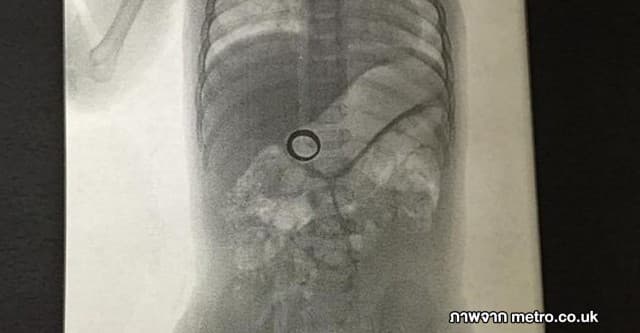

สุดช็อก! แม่ทำแหวนแต่งงานหาย ก่อนพบโผล่ในท้องลูกชาย